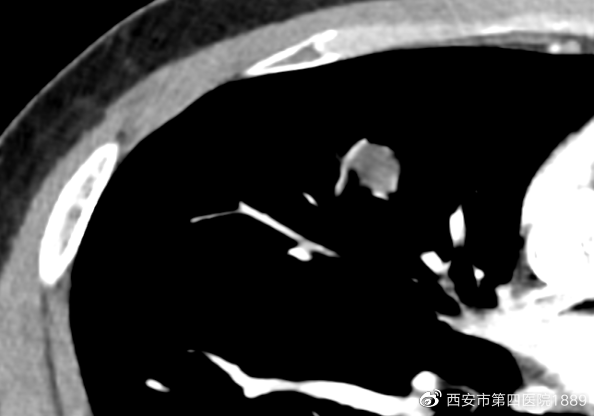

为了更好的了解病灶性质,需全方面观察结节形态、內部组织、血管关系等特点进行判断良恶性。通过CT图像后处理技术联合增强CT,得到病灶的多平面成像,进而从多个角度观察病灶特点,并观察病灶和血管的关系以及强化程度。

胸部增强ct三位重建,先后为矢状位及冠状位。

病灶增强图

通过多平面重建技术,先前右肺中叶在轴位呈现球星结节影,在矢状位及冠状位呈宽基底紧邻胸膜,未见明显胸膜增厚及牵拉,这是良性的表现。但是增强影像可见血管进入,需进一步观察病灶的内部情况。通过DWI(磁共振检查的一种方法)检查发现,患者双侧病灶ADC(抗体-药物结合物)呈高信号,证明该病灶为良性(炎症可能性大)。患者仅需口服莫西沙星1周,1月后复查胸部CT即可。